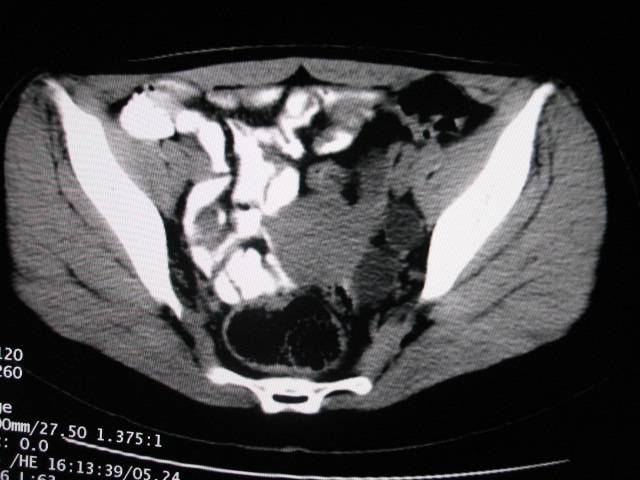

女,28岁,自觉腹部包块一年余

左侧为扩张的输尿管,一直延续到膀胱,那么它的上端应该是扩张的肾盂,但是在他的下方我们看到一个比较正常的肾,所以考虑左侧重复肾盂输尿管畸形。

考虑左侧双肾盂双输尿管畸形,其中一输尿管末端梗阻(不排除异位开口可能)并相应之肾盂及输尿管明显扩张积水。

术后证实是左侧双肾盂双输尿管畸形,巨输尿管巨肾盂症